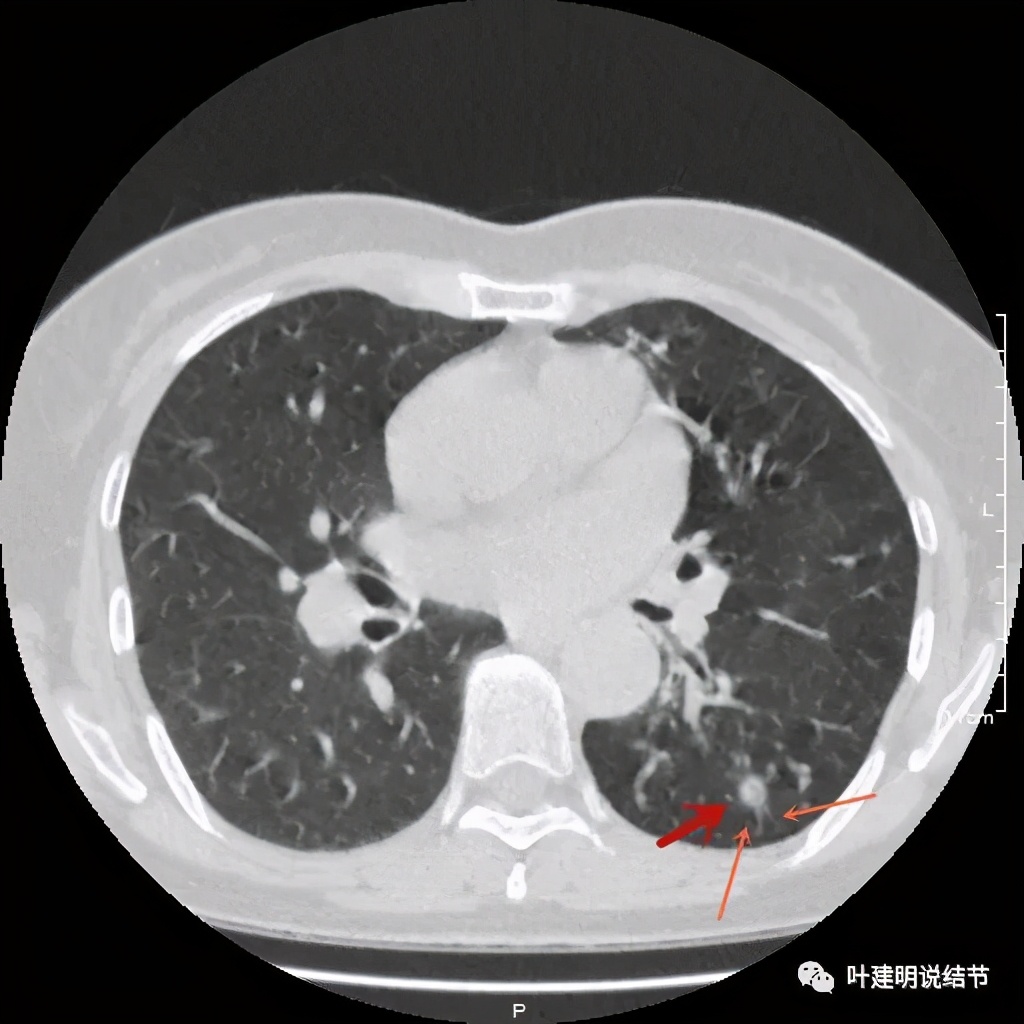

左下肺野多发支气管扩张呈囊状,也有一些实性密度的结节(考虑扩张支气管内的痰栓)。右侧也有实性炎性病灶。所以综合来看,左下之前的结节也得考虑与这些同源,一个原因来解释更为合理,所以恶性的可能性又小了。我建议其随访观察。昨天来复查,我们来看下这次的CT图像:

可见同样部位的左下结节已经较去年密度明显低了一些,说明有所吸收了!基本上已经只是磨玻璃密度了。那么其他病灶的情况呢?

也是有所变化,但病灶仍仍在,是异常的。最后这同图上还见到似乎也是实性伴小空腔的病灶(红色三角形标注处),是不是与之前的病灶有点像?